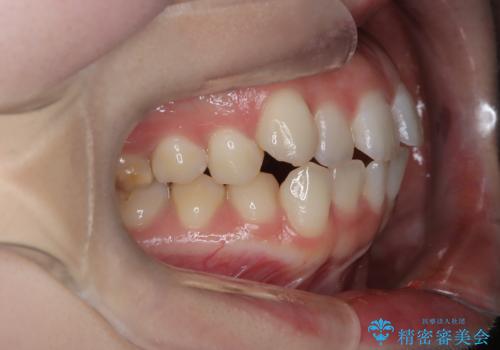

- 右上の八重歯と歯並びのデコボコを気にされて来院されました。精密な検査の結果、歯列のスペースがわずかに不足していることが判明。患者様の「抜歯を避けたい」というご希望を最大限に尊重し、アンカースクリュー(TAD)を用いて奥歯(臼歯部)全体を後方へ移動させることで、八重歯が並ぶスペースを確保する治療計画を立案しました。装置にはワイヤー矯正を使用し、確実で効率的な歯の移動を目指します。

今回のワイヤー矯正治療では、抜歯せずに歯を並べるスペースを作るため、特殊な小さなインプラントであるアンカースクリュー(TAD)を一時的に使用しました。このアンカースクリューを固定源として、奥歯(臼歯部)全体を後方へ遠心移動させました。従来の矯正では難しかったこの奥歯の移動を確実に行うことで、前歯の八重歯を適切な位置に並べるスペースを確保。治療の結果、抜歯することなく右上の八重歯と叢生が解消され、機能的にも審美的にも整った美しい歯並びを獲得していただけました。